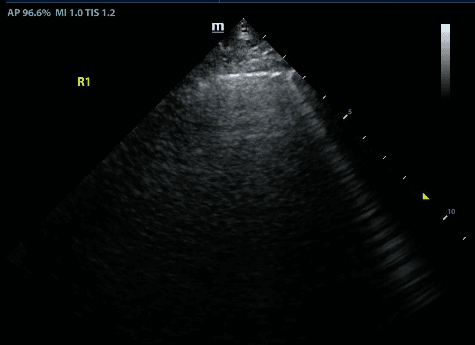

Recall that B lines are vertical hyperechoic artifacts originating from the pleural line that look similar to comet-tails.

B lines reflect interstitial syndrome and the number of B lines increase with decreasing air content in lungs and thus, increasing lung density. To narrow down this broad differential, one can evaluate whether the B lines are present in a diffuse or focal (clumped together) pattern, look at abnormal pleural line patterns and look for other features of abnormal lung on ultrasound.